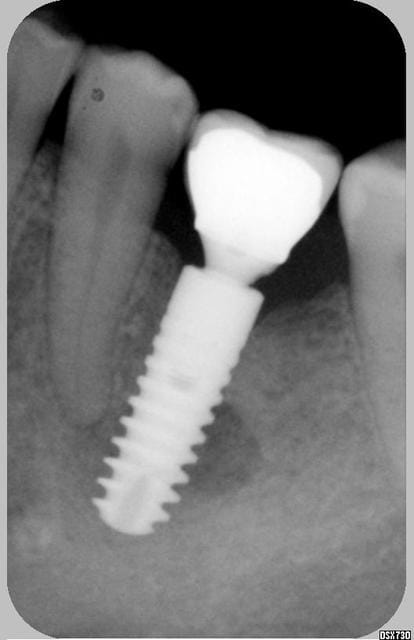

Je revois la patiente aujourd'hui et voila la radio: l'image suspecte a disparu presque complètement, implant complètement silencieux et fixe... todo isso e muito bem!!!

Bien fait de ne rien faire, surtout à cette pôvre prémo !